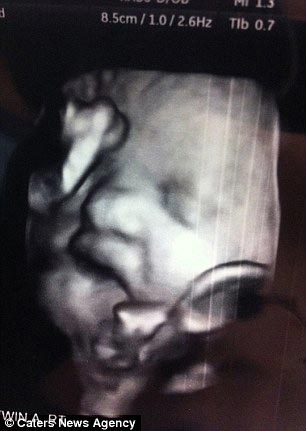

Даже на снимке УЗИ было видно, что рот ещё даже не родившейся девочки уже был открыт по причине слишком большого языка

Не понимая, что девочка больна, во время осмотра техник УЗИ сказал Мелани: "Посмотрите, как мило она показывает вам язык"